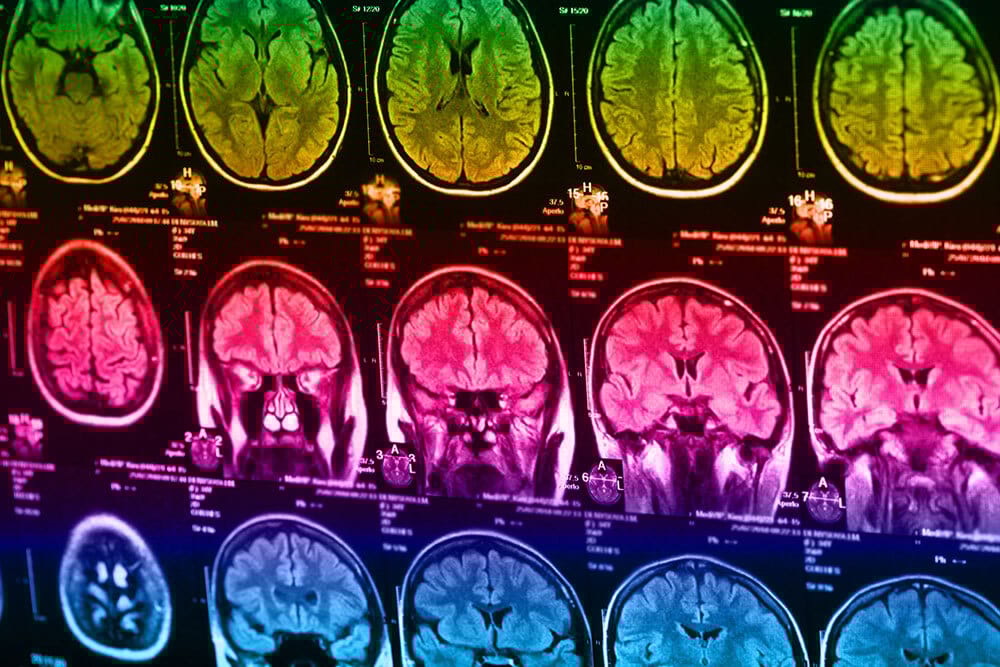

Neuroimaging: Brain Scanning Techniques In Psychology

Neuroimaging is important within psychology to allow in-depth study of what certain areas of the brain are responsible for, as well as being able to identify brain differences in those who may have brain disorders or mental health conditions.